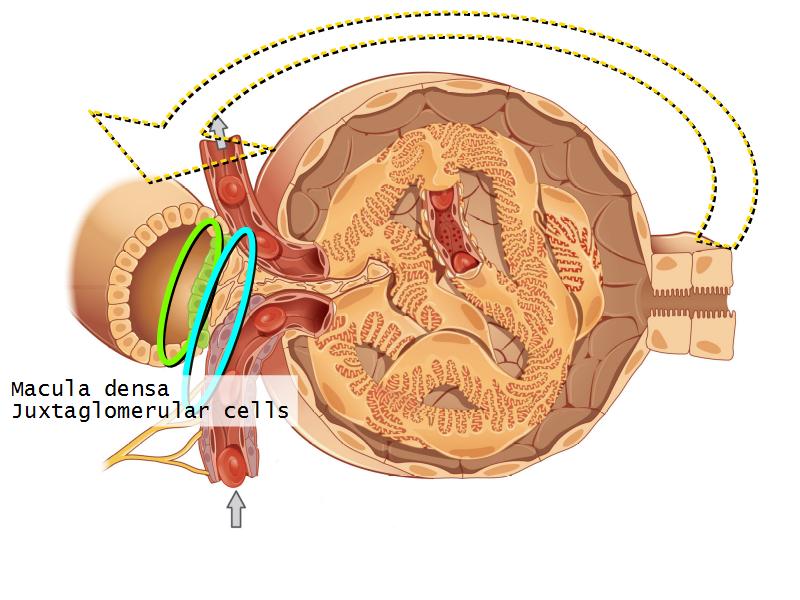

- Basic arrangement of nephrons and collecting tubules in the kidney

- Structure of the nephron and collecting tubules

- The renal corpuscle

- Make an annotated diagram of a nephron, including the juxtaglomerular apparatus. Indicate the flow of blood and water in each part, and how solutes are filtered, secreted and reabsorbed.